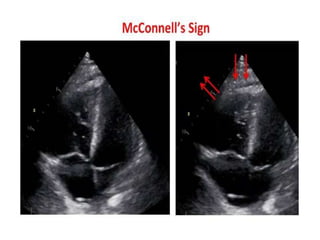

– Echo: RV dilation (apical 4-chamber RV diameter divided by LV

diameter >0.9), or RV systolic dysfunction